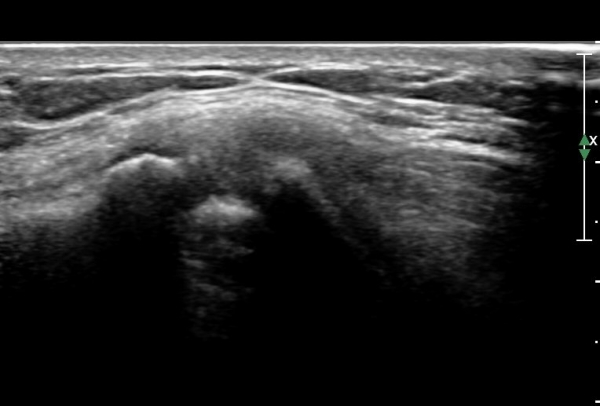

¿ìÃø Èä°ñ¼â°ñ°üÀýÃÊÀ½ÆÄ°Ë»ç¿¡¼­ °üÀýÀÇ ÅðÇ༭ º¯È­°¡ °üÂûµÊ(»çÁø 3, 4).